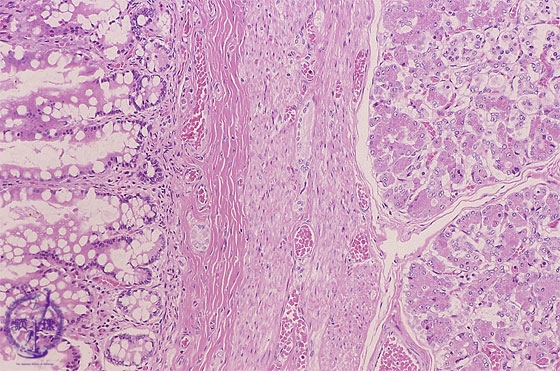

Microscopic view, high power; The inner lining is covered by mucosa resembling that of the small intestine with pancreatic tissue is present in the wall (arrow)

Click the image to see the enlarged image.